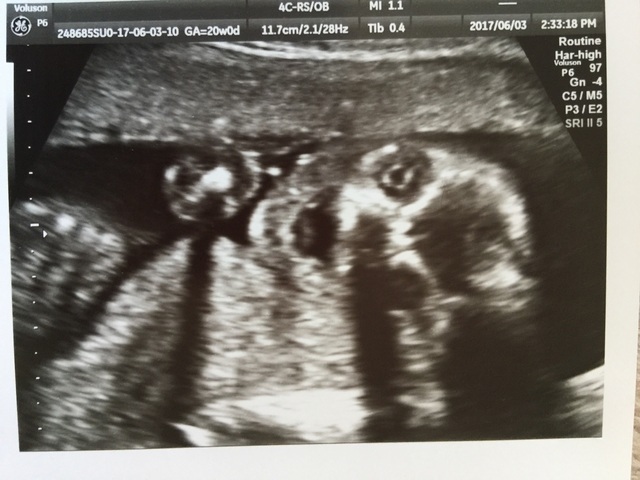

20週1日(20w1d・女の子)|Sato3_n さん(33歳)

エコー写真撮影時のエピソード:

まだまだ小さいのに難しい顔して頭をポリポリかいたり、大きなあくびをしてバンザイしたり、とても表情豊かで主人とみていて笑えました!

何を考えているのかな?!とてもかわいくて愛おしいです。会える日が楽しみです!